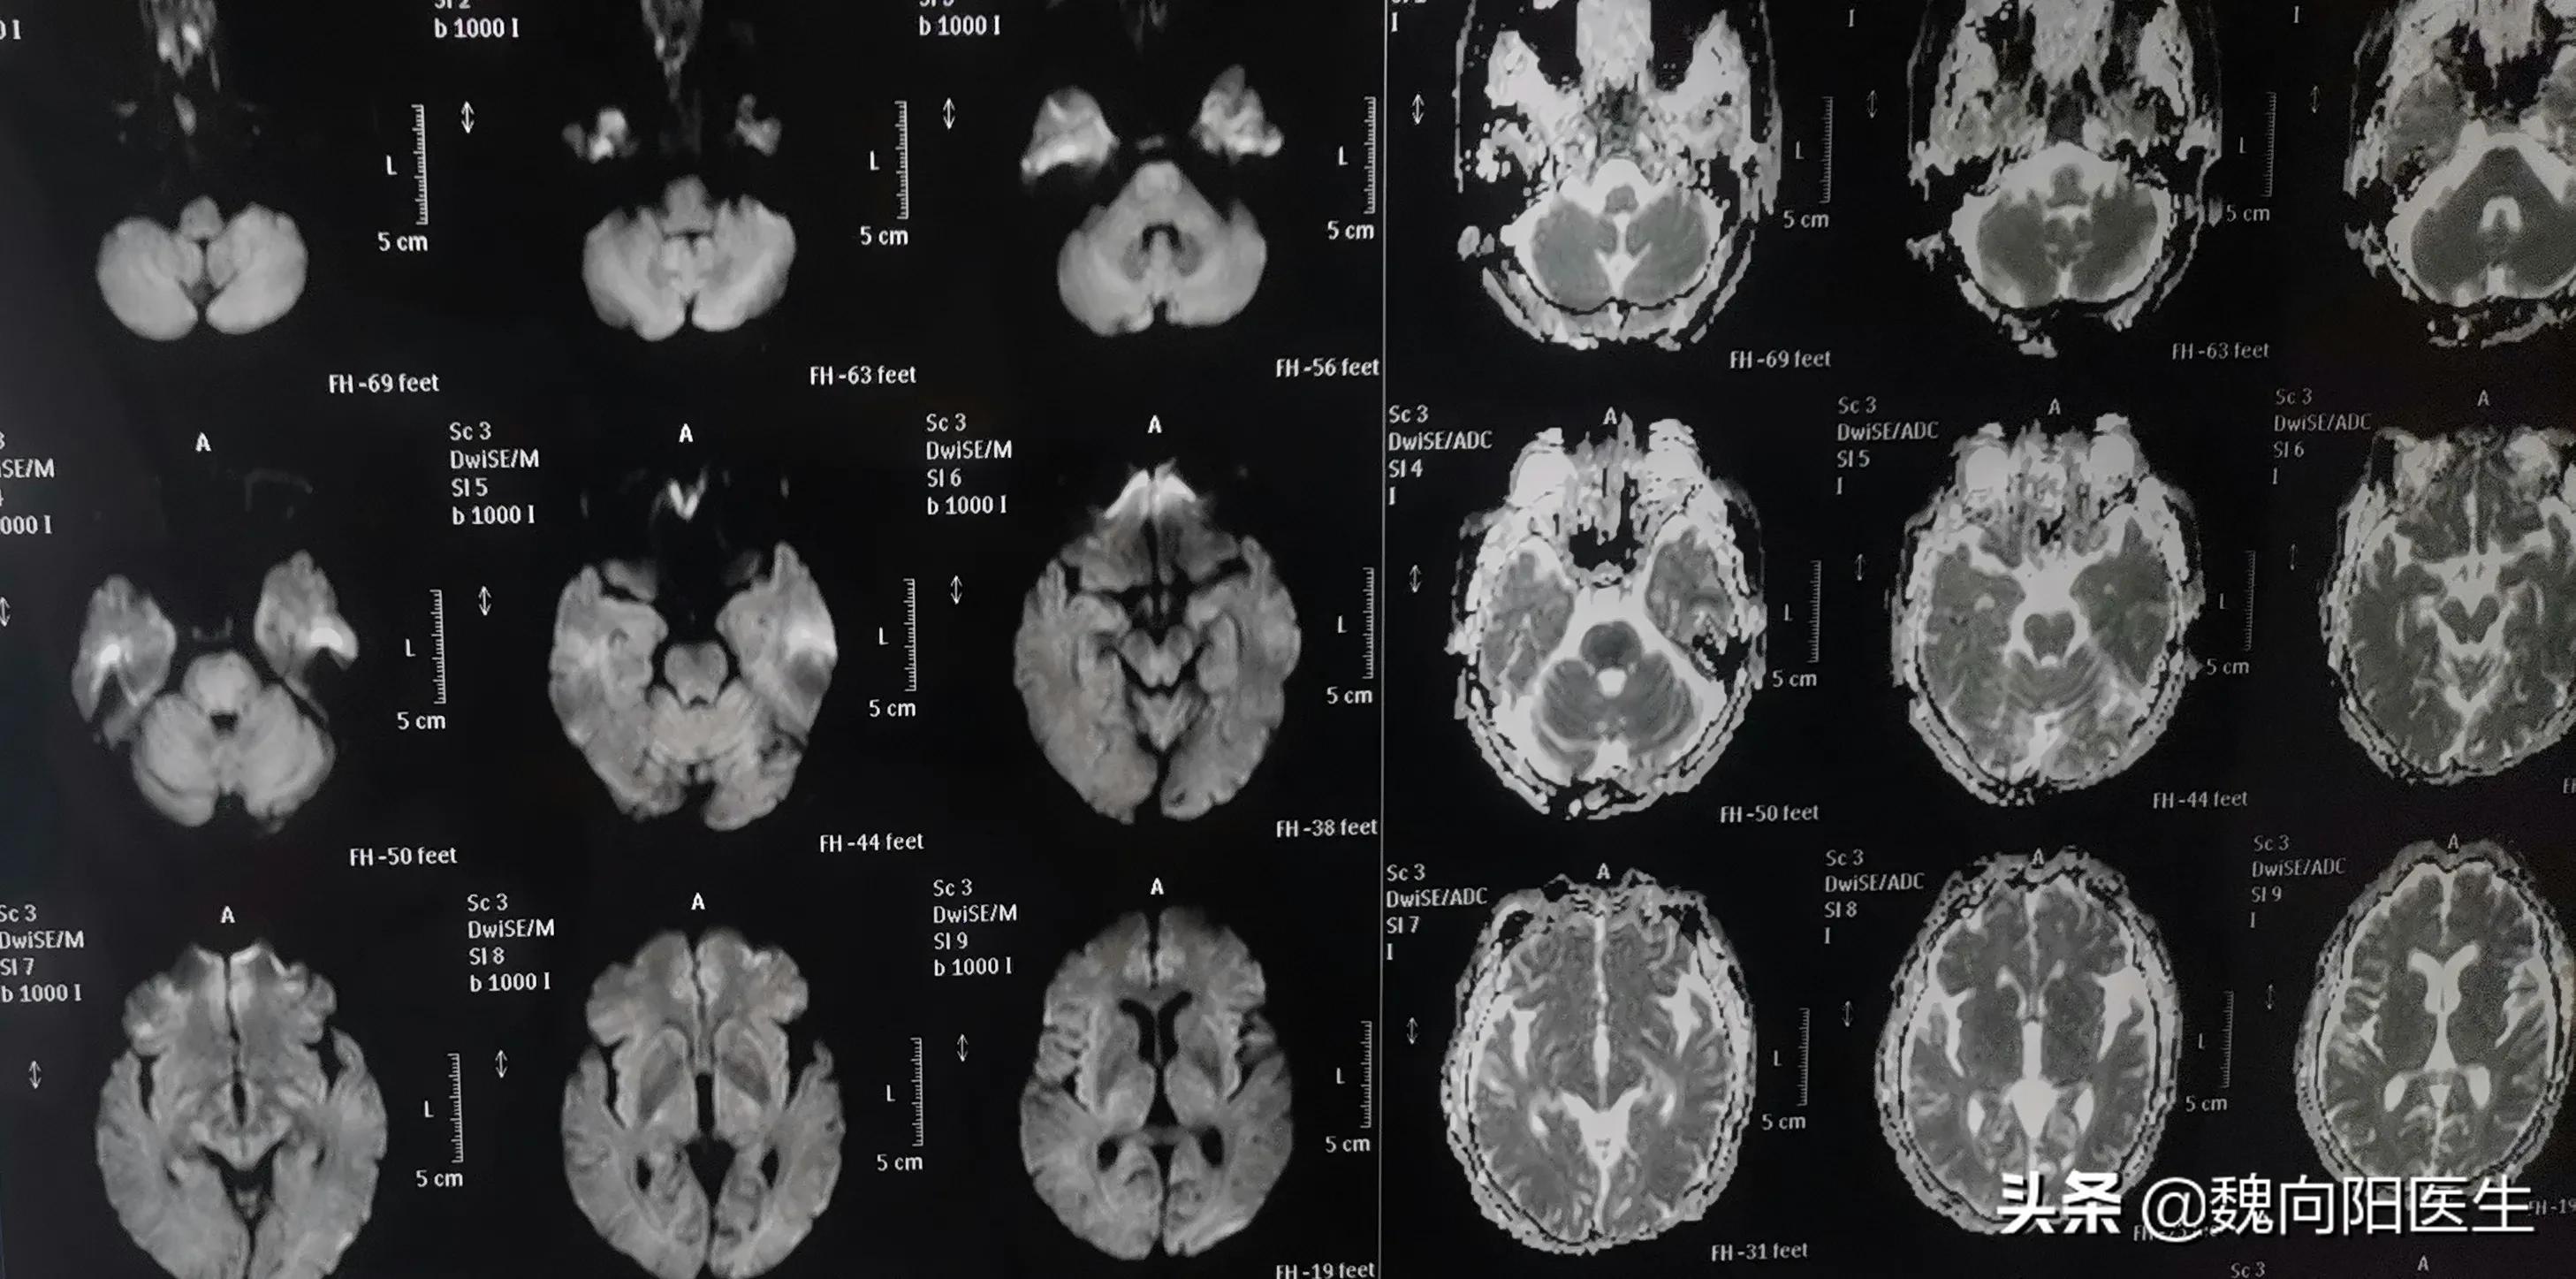

今天急诊收了63岁女性患者,突发意识不清三个小时,头核磁提示:“脑干梗死,椎动脉不显影”。#脑梗死##脑卒中#

诊断:脑干梗死。